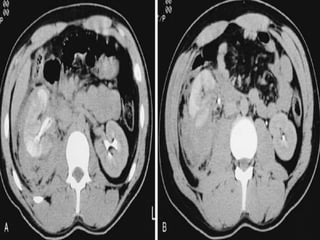

Computed tomography

Imaging study of choice for hemodynamically stable

patient

Advantages

(1) Functional and anatomic assessment of the kidneys

and urinary tract

(2) Establish the presence or absence of 2 functional

kidneys

(3) Diagnosis of concurrent injuries

(4) Delineates extravasations, segmental infarcts, and

hematoma